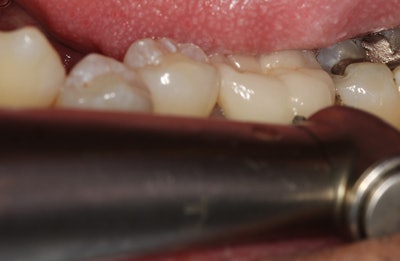

The patient in this case presented with a nonrestorable, root canal-treated mandibular molar tooth (figures 1-3). After patient consultation, it was decided that the tooth would be extracted and grafted in preparation for a dental implant.

Since the roots were divergent and it was a mandibular molar tooth where the bone is more dense, the treatment plan included the following:

- The crown would be removed.

- The tooth would then be sectioned and extracted as individual roots.

- The site would then be grafted with a simple technique in preparation for a future dental implant.